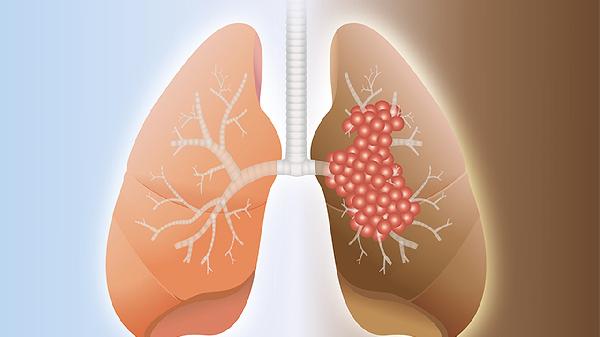

鼻病毒属于呼吸道病毒,通常局限于上呼吸道感染,表现为鼻塞、流涕、咽痛等症状。病毒本身对肺部组织的侵袭性较弱,健康人群感染后多呈自限性过程。但若患者存在慢性阻塞性肺疾病、哮喘等基础病,或婴幼儿、老年人等免疫力较弱群体,病毒可能破坏呼吸道屏障功能,继发细菌性肺炎。常见继发感染的病原体包括肺炎链球菌、流感嗜血杆菌等。